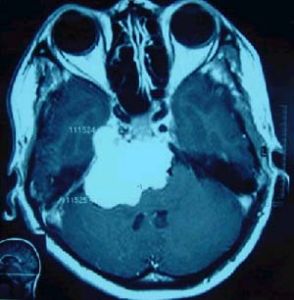

圖1 岩骨斜坡腦膜瘤1.頭痛 頭痛多限於枕頂部,也有頭頂部疼痛,有時為首發症狀。

2.CT檢查 CT和MRI是診斷該區腦膜瘤最有效的手段,在檢查中均要做注藥對比強化掃描,否則有誤診的可能。CT平掃上主要表現為岩骨斜坡區分葉狀或卵圓形均勻高密度或略高密度占位性病變,少數腫瘤混有大小不等的低密度灶。注射造影劑後可均勻強化,多表現為圓形、卵圓形或不規則型、 腫瘤與硬腦膜以廣基相連,局部可有骨質增生或骨質破壞,有時表現為岩尖部明顯破壞。此外CT還可顯示乳突氣化的程度和骨迷路的位置,有利於指導手術。

3.MRI檢查 大多數腦膜瘤的信號與腦灰質相似,在T1加權像上多數為等信號,少數表現為低信號;在T2加權像上可表現為高、等、低信號,注射Gd-DTPA後絕大部分腫瘤出現強化,大部分腦膜瘤與相鄰腦組織特別是腦幹有包膜相隔。另外MRI在顯示腦膜瘤與鄰近血管關係上明顯優於CT,可以用三維立體方式清楚地顯示腫瘤的位置、大小,腫瘤的侵犯方向,有無基底動脈及分支受累。更重要的是在T2加權像上, 可觀察瘤周的蛛網膜層是否存在,有無腦幹軟膜侵犯, 有無腦幹水腫,這對於疾病的術前評估是十分重要的(圖1) 當腦膜瘤包繞或擠壓頸內動脈、基底動脈時,由於血管內快速流動的血液產生流空現象,在T1和T2加權圖像上均為低信號區。